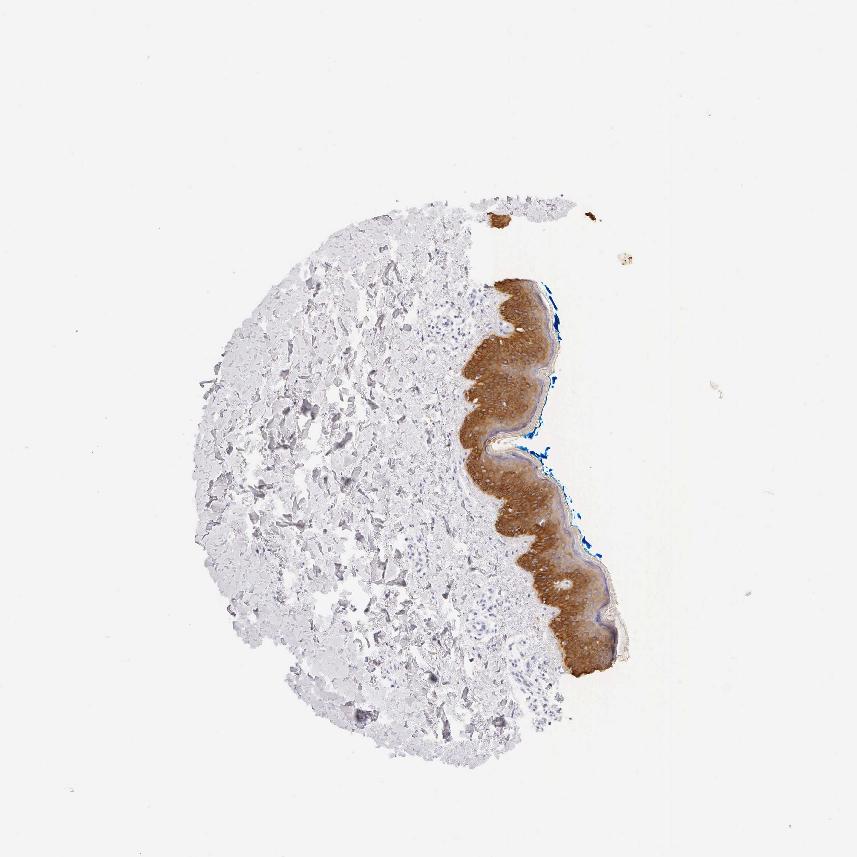

SKIN 1 - Antibody stainingi

Antibody staining in the annotated cell types in the current human tissue is reported as not detected, low, medium, or high, based on conventional immunohistochemistry profiling in selected tissues. This score is based on the combination of the staining intensity and fraction of stained cells.

Each image is clickable and will lead to virtual microscopy that enables deeper exploration of all samples and also displays staining intensity scores, fraction scores and subcellular localization as well as patient and tissue information for each sample.

Antibody HPA000452Antibody HPA000453Antibody HPA045062Antibody CAB000029

Keratinocytes MediumHigh-Not detected

Sebaceous glands --High-